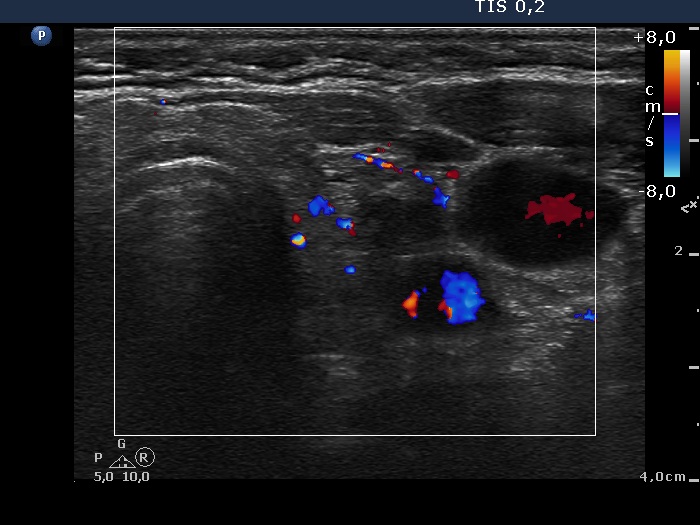

Discrete lesion or nodule in Hashimoto's thyroiditis - case 14 (377) (ultrasonographic picture 8)

Left lobe, transverse scan, color Doppler mode. The vascularization is not specific.